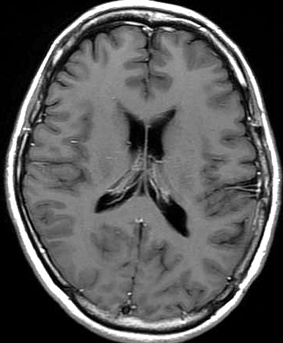

手術後のMRIです。腫瘍は全部取れていて後遺症もありません。圧迫されて変形していた脳はきれいに元に戻っていますし脳浮腫も消えました。一般的に若い人の脳ほどきれいに元に戻ります。注意しなければならないのは,少しでも取り残した場合には,何年か後に10%-20%くらいで再発があることです。もちろん完全に取れた時の再発はほとんどありません。